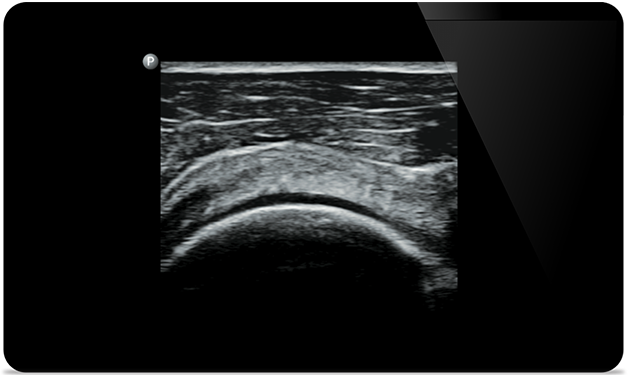

Padstatic case example image

Start treatment with an accurate diagnosis

Start treatment with an

accurate diagnosis

Lumify helps you see the fine details in muscles, joints, ligaments, tendons and cartilage to make a more accurate diagnosis of injuries.